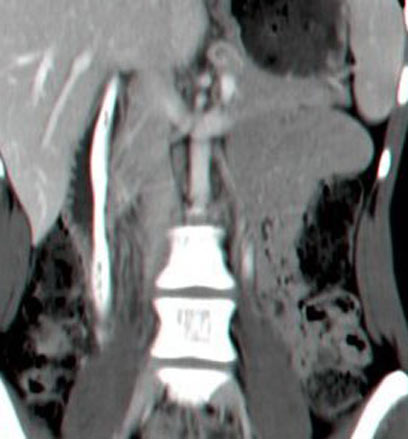

הידית התקועה ברנטגן (צילום: רדיט, ד"ר יעקב גוטלר)

"מייד בקבלתה לבית החולים נבדקה המטופלת בחדר המיון ובוצעה בדיקת הדמיה של הבטן, בה נצפתה ידית מברשת שיניים בשלמותה באורך של 14 ס"מ בתריסריון", סיפר ד"ר אהוד מלצר, מנהל המכון הגסטרואונטרולוגי בקפלן. "לאחר התייעצות מהירה בוצעה בדיקת גסטרוסקופיה ובה נצפתה הידית בתריסריון בשלמותה כשהיא תקועה בין דופן אחת לשנייה ועלולה הייתה לחדור בכל רגע את דופן התריסריון, מצב שהנו מסכן חיים".